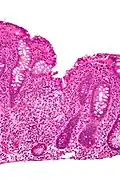

Cryptitis. H&E stain.

Cryptitis. H&E stain. -